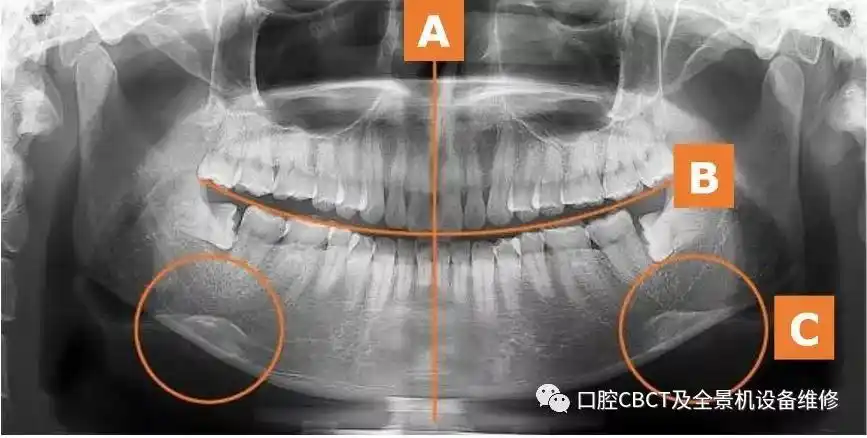

口腔ct全景机操作规程